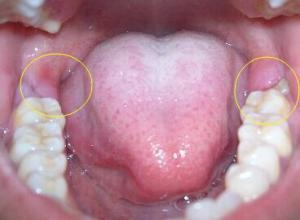

磨牙后区发炎的图片

磨牙后区发炎的图片,磨牙图片

智齿发炎疼痛怎么办?看这一篇就够了!(已收藏)

智齿发炎图片